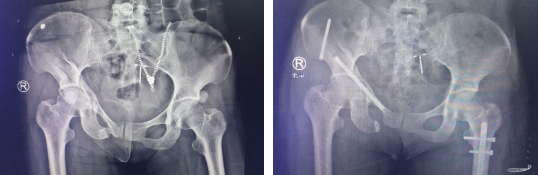

胡女士是车祸后4小时被送到必威官方首页官网betway的,当时左大腿出血畸形,右髋疼痛,左髋关节活动受限,急诊摄片显示左股骨骨折,骨盆多发骨折。

进行双侧胫骨结节骨牵引术一周后,胡女士恢复良好。随后,创伤骨科任海东主任周立国朱宏医生团队操作天玑骨科机器人成功对胡女士实施了骨盆骨折复位内固定术。术中,任主任团队对胡女士进行三维影像扫描,并将影像数据同步传输给了骨科手术机器人系统。

在骨科机器人的精确定位下,手术医生沿着套筒钻入导针,确认位置无误后,再沿导针打入前柱螺钉固定,拔出导针。再次对胡女士进行扫描,成功了!螺钉位置与既定规划完全一致!如今,胡女士恢复良好,已经出院。